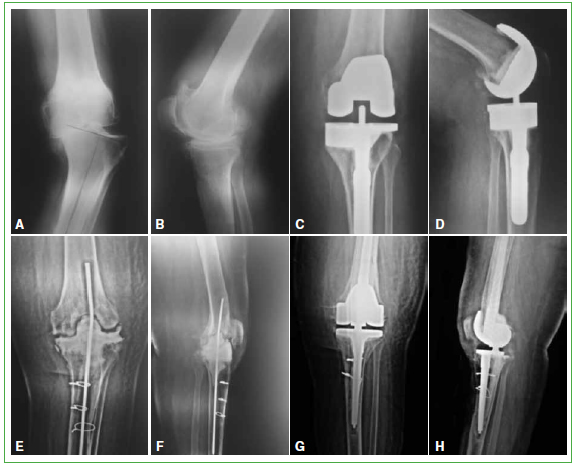

Figura 1.

Caso 15. A y B. Genu varo severo. C y D. Artroplastia total de rodilla con aumento tibial medial y vastago no cementado. E y F. Primer tiempo de revision por aflojamiento septico. Osteotomia de la tuberosidad anterior de la tibia y colocacion de un espaciador no articulado. G y H. Segundo tiempo de revision con una protesis abisagrada total de rodilla.

Todas las rodillas fueron evaluadas con el Knee Society Score (KSS) antes de la cirugia y en el posoperatorio.12 Para medir el rango de movilidad se empleo un goniometro con el paciente en decubito dorsal antes de la cirugia y en el posoperatorio. Las radiografias posoperatorias fueron evaluadas buscando signos de aflojamiento. Se administraron 2 g de cefazolina como profilaxis antibiotica, y 15 mg/kg de acido tranexamico antes de la cirugia y una segunda dosis en el momento del cierre.13 En ningun caso, utilizamos manguito hemostatico. La incision cutanea se realizo en la linea media, en el caso de las revisiones usamos la incision previa y, si habia mas de una, la mas lateral. Los seis pacientes con un severo deseje en valgo fueron operados a traves de un abordaje pararrotuliano externo.14 En el resto de los casos de cirugia primaria, como en todas las revisiones, utilizamos un abordaje pararrotuliano interno. En 18 casos (53%), usamos un recorte en el tendon del musculo recto anterior o “rectus snip” para facilitar la exposicion. En el caso 15, durante una revision, fue necesario realizar una osteotomia de la tuberosidad anterior de la tibia para facilitar la extraccion del vastago tibial (Figura 1). Siempre usamos vastagos cementados y cemento con antibiotico. Solo, en casos seleccionados, implantamos el componente rotuliano segun su compromiso degenerativo en las cirugias primarias y el remanente oseo en las revisiones. Como profilaxis antitrombotica, se administraron 40 mg/dia de heparina de bajo peso molecular, por via subcutanea, durante 30 dias, a partir de las 12 h posoperatorias. El protocolo de rehabilitacion consistio en ejercicios de movilidad de la rodilla y marcha con andador con carga segun tolerancia, a partir de las 48 horas.